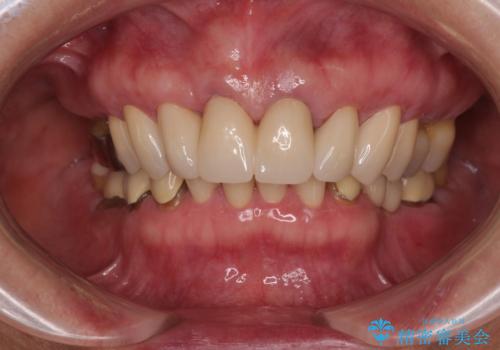

【海外から通院】統一感のない前歯をきれいに オールセラミッククラウン治療

帰国時のみの治療であったため、治療期間は長くなりましたが、最小限の来院回数で、気になっていた前歯をきれいに整えることができました。